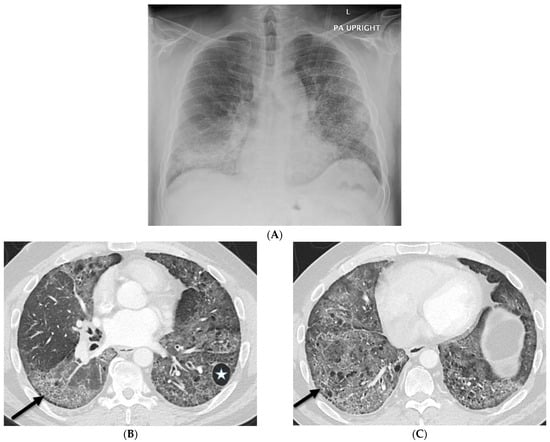

6.2. Pulmonary Alveolar Proteinosis (PAP)

| Pulmonary alveolar proteinosis (PAP) | smooth | + | ++ | + | − | − | − | +/− | − | − |